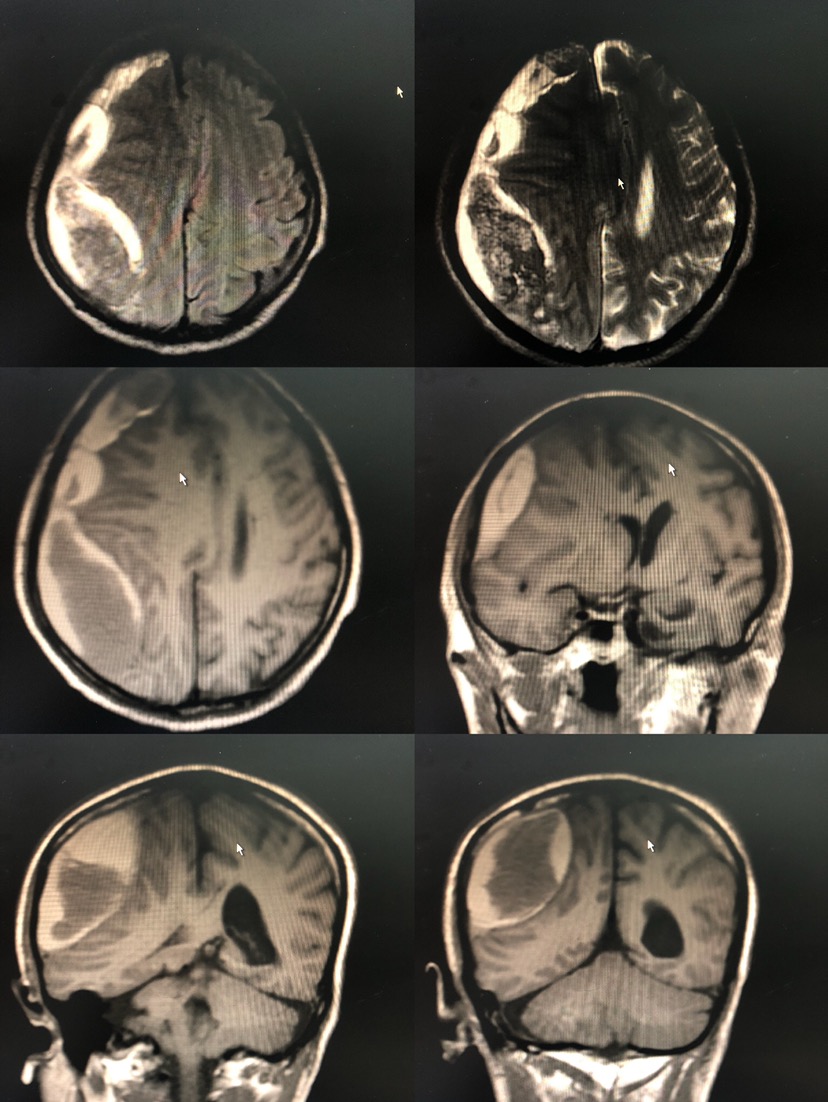

如图所见,CT及MRI提示均为硬膜外血肿。

但根据患者病情及以往所见仍考虑硬膜下可能。

思考:1、该患者属慢行硬膜下血肿,长期刺激形成包膜,影像学表现呈梭形,易误认为硬膜外。